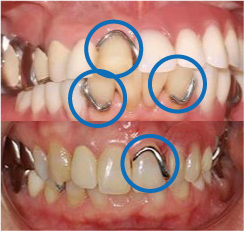

そのため、下記写真(青い丸で囲った部分)のような金属やつまみが付くことになります。

しかしKIさんの場合、左側の奥歯が既に5本ブリッジとなっており、使えない状態となっていました。

そのため、保険の義歯を作成することになりました。

実際に保険の義歯を装着してみると、義歯がガタついて揺れる、ものが詰まる、金属が気になって話し辛いなどの弊害が出てきてしまいました。